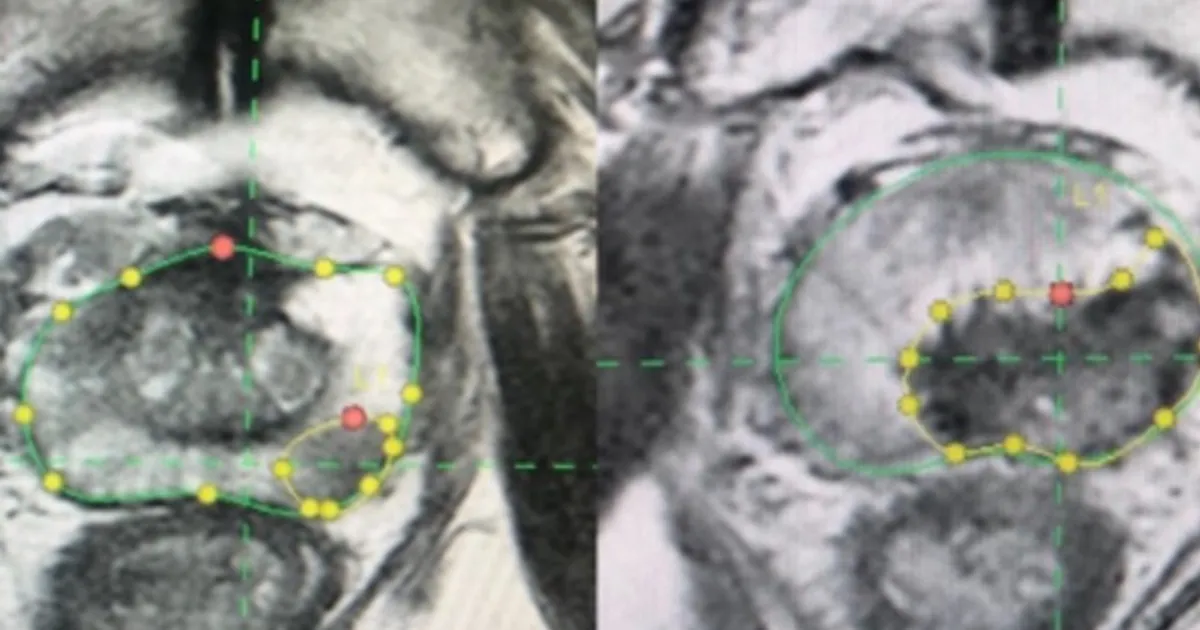

أجري العلاج تحت التخدير العام كإجراء ليوم واحد فقط. واعتمد التخطيط المسبق لمنطقة الاستئصال على صور الرنين المغناطيسي، مع إضافة هامش أمان لا يقل عن 5 ملليمتر حول الورم.

واستخدمت تقنيات توجيه مختلفة، شملت التوجيه الروبوتي في غالبية الحالات، أو دمج صور الأشعة المقطعية والرنين المغناطيسي مع الموجات فوق الصوتية.